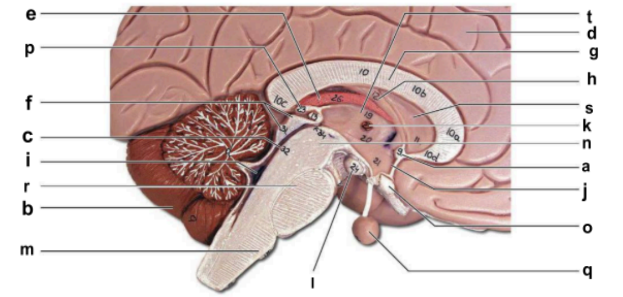

Identify the structure labeled “a” in the image.

anterior commissure

Identify the structure labeled “b” in the image.

cerebellum

Identify the structure labeled “c” in the image.

cerebral aqueduct

Identify the structure labeled “d” in the image.

cerebral hemisphere

Identify the structure labeled “e” in the image.

choroid plexus

Identify the structure labeled “f” in the image.

corpora quadrigemina

Identify the structure labeled “g” in the image.

corpos callosum

Identify the structure labeled “h” in the image.

fornix

Identify the structure labeled “i” in the image.

fourth ventricle

Identify the structure labeled “j” in the image.

hypothalamus

Identify the structure labeled “k” in the image.

interthalamic adhesion

Identify the structure labeled “l” in the image.

mammilary body

Identify the structure labeled “m” in the image.

medulla oblongata

Identify the structure labeled “n” in the image.

midbrain

Identify the structure labeled “o” in the image.

optic chiasma

Identify the structure labeled “p” in the image.

pineal gland

Identify the structure labeled “q” in the image.

pituitary gland

Identify the structure labeled “r” in the image.

pons

Identify the structure labeled “s” in the image.

septum pellucidum

Identify the structure labeled “t” in the image.

thalamus